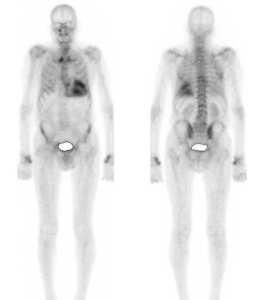

En suivant l’algorithme diagnostic de l’ESC, nous avons réalisé une scintigraphie aux bisphosphonates (Figure 5).

Figure 5 : Résultats de scintigraphie corps entier au DPD montrant une hyperfixation cardiaque avec extinction de la trame osseuse = stade PERUGUINI 3

Le score de PERUGUINI utilisé dans l’amylose permet une évaluation semi-quantitative de l’intensité de fixation du traceur osseux dans le myocarde1 (Figure 6).

- Grade 0 : absence de fixation cardiaque du traceur

- Grade 1: fixation cardiaque faible < au signal des côtes

- Grade 2: fixation cardiaque = au signal des côtes

- Grade 3: fixation cardiaque > au signal des côtes associée à une diminution de la fixation globale osseuse du traceur

Figure 6 : Scintigraphie osseuse